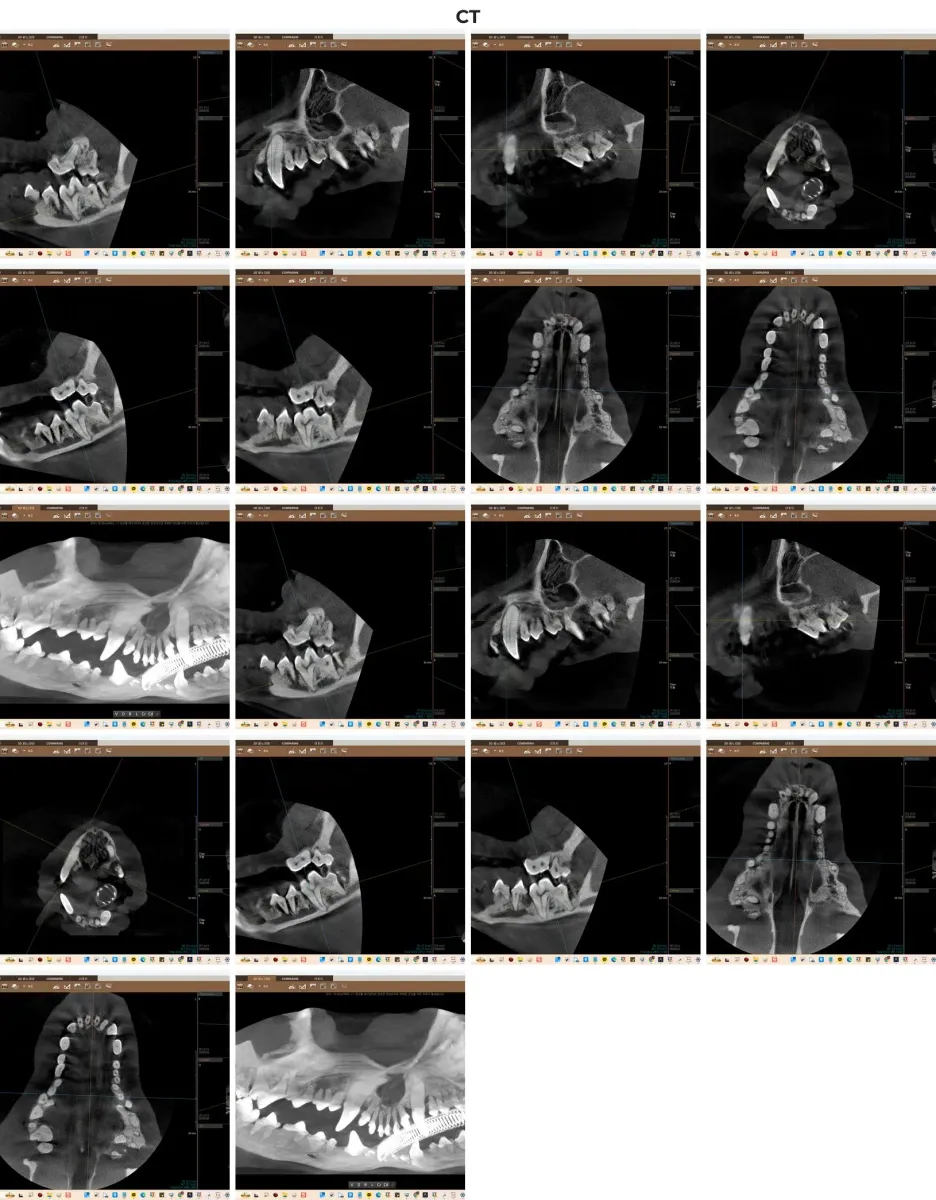

강아지의 치아 질환은 육안으로 보이는 잇몸 위쪽보다 잇몸 아래, 즉 치근(뿌리)과 치조골(잇몸뼈)의 상태가 훨씬 중요합니다. 일반적인 검사로는 놓치기 쉬운 3차원적인 뼈의 결손, 치아 뿌리의 미세한 염증(치근단 병변) 및 해부학적 구조물과의 관계를 정확히 파악하기 위해서는 동물 전용 치과 CT 촬영이 필수적입니다. 금호동물병원은 광주 전남 유일 치과 CT를 도입하여 가장 안전하고 정밀한 수술 계획을 수립합니다.

치과 전용 CT를 통한 3차원 정밀 진단 스캔 이미지

정확한 진단을 위해 마취 전 검사를 거친 후, 구강 방사선(X-ray) 촬영과 정밀 치과 CT 스캔을 진행했습니다. 검사 결과는 예상보다 심각했습니다. 대다수의 치아에서 치조골 흡수(ABL2 단계 이상)가 확인되었으며, 특히 108번, 109번, 208번, 209번 등 주요 어금니 부위에서는 치주 인대 소실 및 뿌리 끝 염증(PA3)이 관찰되었습니다. 치아를 지지해 주어야 할 뼈가 녹아내려 발치가 불가피한 상황이었습니다.